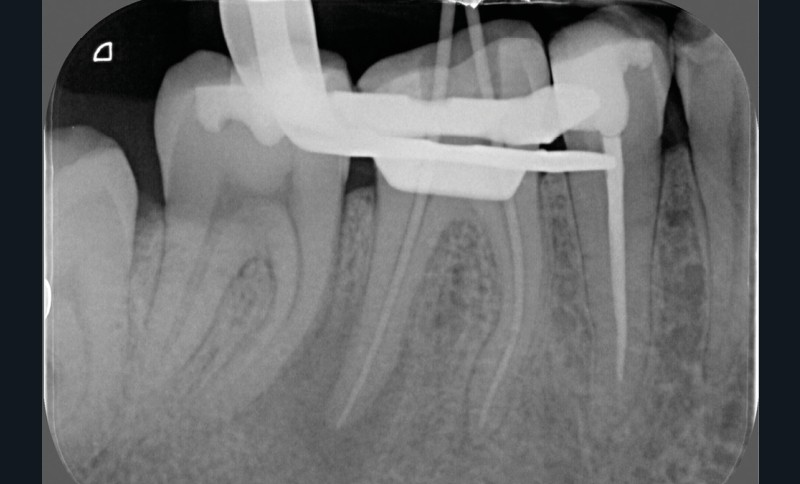

La préparation mécanique est principalement réalisée à l’aide d’instruments NiTi utilisés en rotation continue ou en réciprocité selon une approche corono-apicale. La mise en forme est ainsi plus rapide et respecte mieux le trajet canalaire initial qu’avec une instrumentation manuelle. Le diamètre apical et la conicité de la préparation canalaire font toujours débat. Ils dépendent de l’anatomie initiale et doivent permettre une irrigation efficace sans fragiliser la dent. Ainsi, un diamètre apical de 30 et une conicité de 6 % sont souvent proposés comme objectif minimal à atteindre [3] (fig. 1).